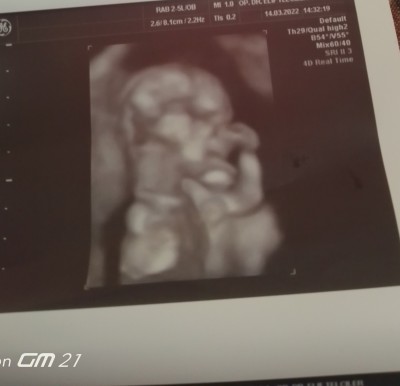

Slm herkese 19+3 hamileyim cinsiyet tahmini yapabilirsiniz

Gebelik haftası 19+4

Kız geçti canım içimden :))